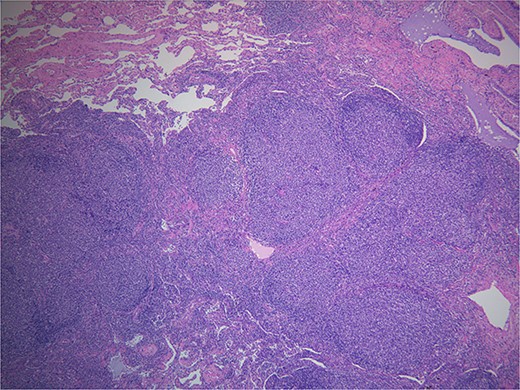

Final pathology with immunostaining ultimately revealed a follicular lymphoma. Figure 1 highlights the neoplastic follicles within the lung tissue with decreased macrophage bodies. Immunostains for CD 20 and CD3 highlighted B cells and reactive T cells around the neoplastic follicles (Fig. 2a and b). Other immunohistochemistry findings were notable for negative BCL2 and CD10. Molecular fluorescence in situ hybridization testing also detected BCL6 gene rearrangements. Overall, the histology and immunohistochemical findings are diagnostic of atypical follicular process combined with monoclonal IgH gene and BCL6 positive gene rearrangements, consistent with follicular lymphoma.

Hematoxylin and eosin. Demonstrates back to back neoplastic follicles within lung tissue.